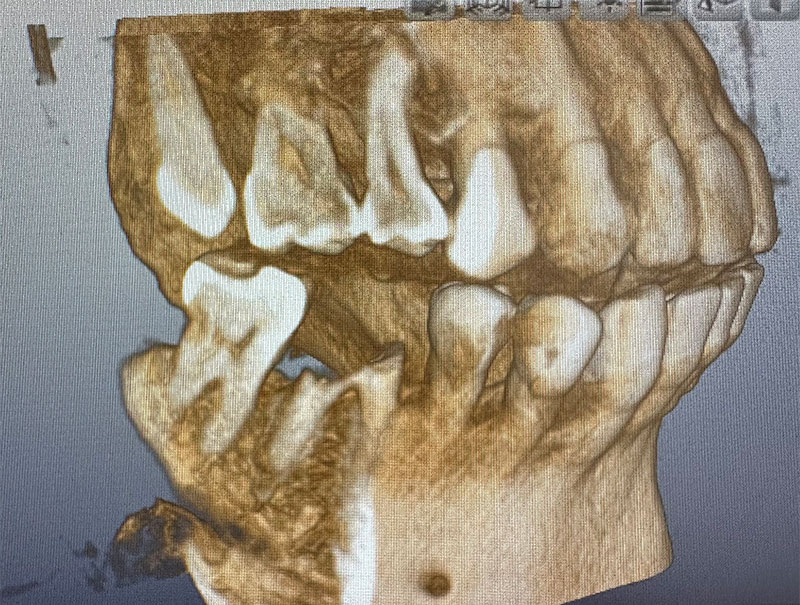

レントゲン写真およびCT画像なのですが、右上6が残歯状態であり歯根破折を起こしている状態でした。しかし歯槽骨から上顎洞底までの距離は十分に認められます。この歯槽骨から上顎洞までの距離がないとソケットリフトなどのオプションの処置が必要になってくるのですが、今回の症例では大掛かりな処置の必要はなく症例の難易度としては比較的イージーな方でした。上顎洞などに関して知りたい方はこちらのページを参照にしていただければと思います。